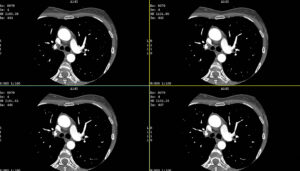

Cardiac calcium scoring (also called coronary artery calcium scoring, CAC scoring, or heart scan) is a specialized CT scan that measures calcified plaque buildup in your coronary arteries, the blood vessels that supply oxygen to your heart muscle. This quick, non-invasive screening detects atherosclerosis (hardening of the arteries) before symptoms appear, helping predict your risk of heart attack and coronary artery disease.

Cardiac calcium scoring detects and quantifies coronary artery calcification, a marker of atherosclerotic plaque buildup in the arteries supplying your heart muscle. This is the underlying disease process responsible for most heart attacks.

Calcium scoring predicts future heart attack risk and overall cardiovascular disease burden but does not detect soft plaque or active blockages.